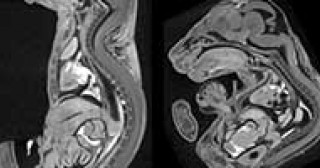

脊椎後弯や肋骨形成異常を引き起こす新たな遺伝子変異をマウスで発見